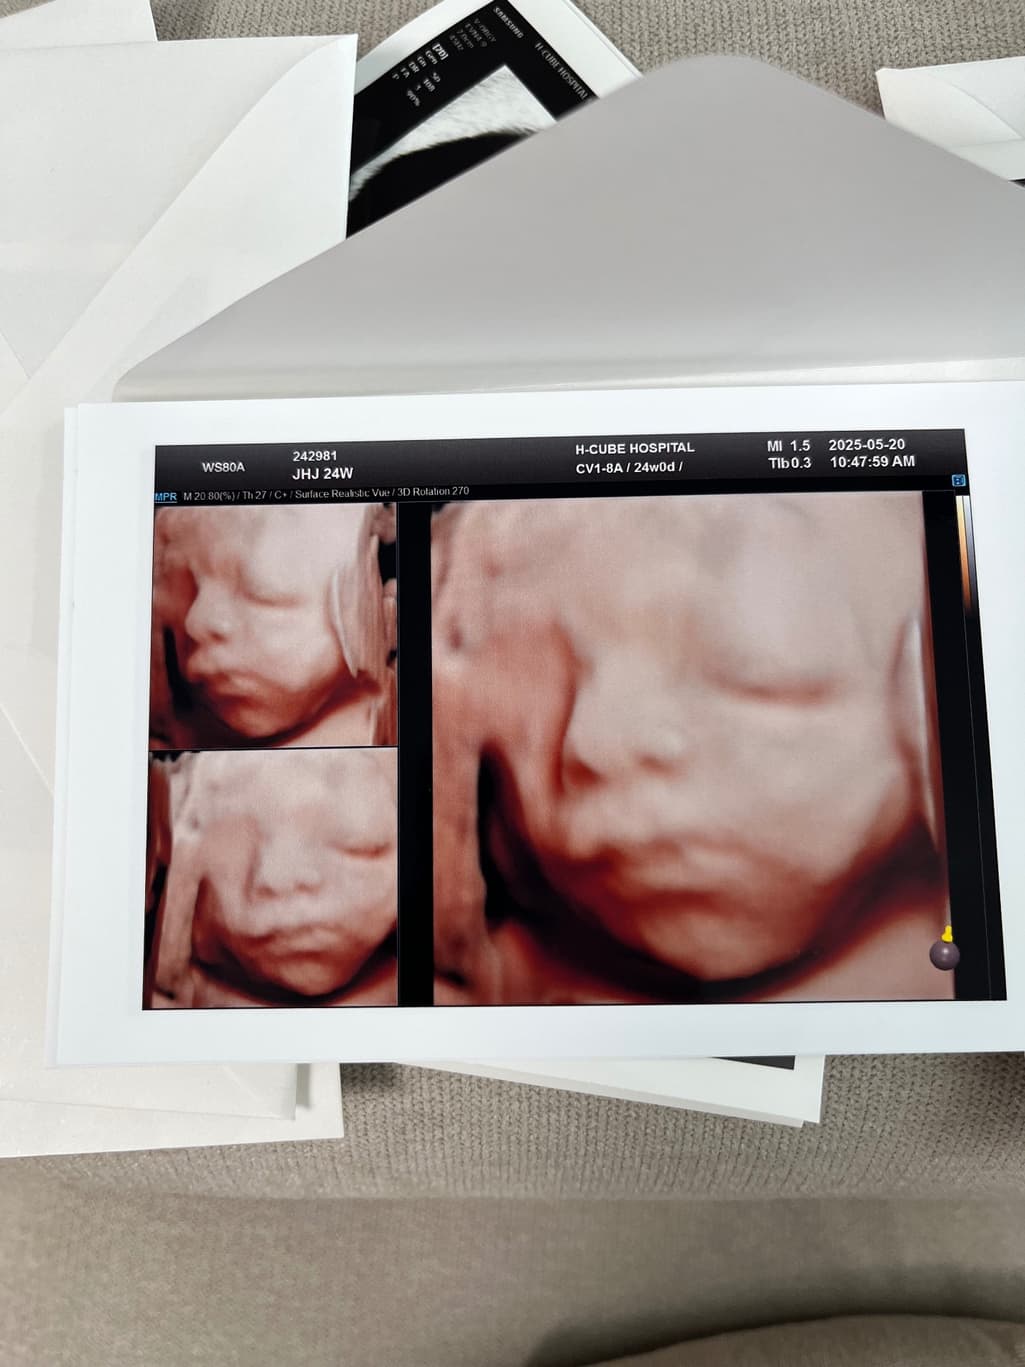

안녕하세요, 사진 순으로 24주차 입체초음파, 그 다음 두 장은 36주차 일반 초음파 사진입니다.

다름이 아니라 36주차 사진상 아이 눈 간격이 너무나 좁아보여서 걱정이 되어서 여쭈어봅니다..

옆으로 눌린 자세라 일시적으로 그렇게 보일 수 있는건지, 아니면 실제 저렇게 눈 간격이 좁은 아이의 경우도 있는지 궁금합니다.